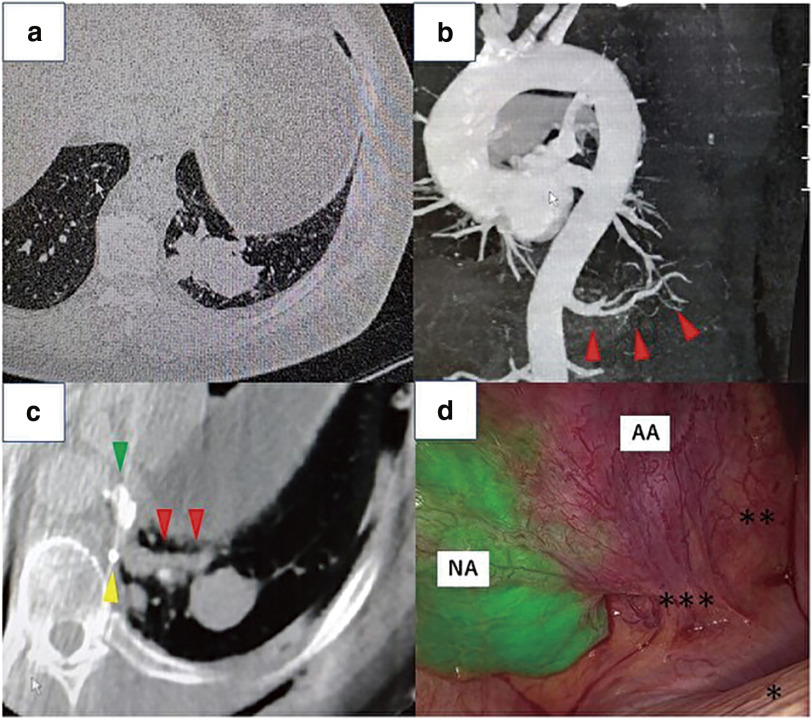

正常肺部的全身动脉供血是一种罕见的解剖异常。由于这种异常会导致肺动脉高压,因此通常需要进行手术。在此,我们报告了我们的经验和安全血管解剖的想法。病例 1 是一名 50 多岁的女性。我们在经皮线圈栓塞术后进行了左肺下叶切除术。术中通过锥形束计算机断层扫描(CBCT)确认了带有栓子的异常动脉,以便在胸腔镜手术(TS)下安全地剥离。病例 2 是一名 40 多岁的男子。经皮血管内栓塞闭塞后,我们使用吲哚青绿荧光导航进行了左侧部分切除术。术中,CBCT 成像显示了异常动脉和栓子的确切位置。这种介入放射学和TS与CBCT成像相结合的技术被认为是治疗正常肺部异常系统动脉供血的安全可靠的方法。

Systemic arterial blood supply to a normal lung is a rare anatomical abnormality. Surgery is usually indicated because this abnormality leads to pulmonary hypertension. Herein, we report our experience and ideas for safe vessel dissection. Case 1 was a woman in her 50s. We performed a left lower lobectomy following percutaneous coil embolization. The aberrant artery with emboli was confirmed intraoperatively by cone-beam computed tomography (CBCT) to safely dissect under thoracoscopic surgery (TS). Case 2 was a man in his 40s. Following percutaneous endovascular plug occlusion, we performed a left partial resection using indocyanine green fluorescence navigation. Intraoperatively, CBCT imaging demonstrated the aberrant artery and exact position of the emboli. This combination technique of interventional radiology and TS with CBCT imaging was considered safe and more secure for the treatment of anomalous systemic arterial blood supply to a normal lung.